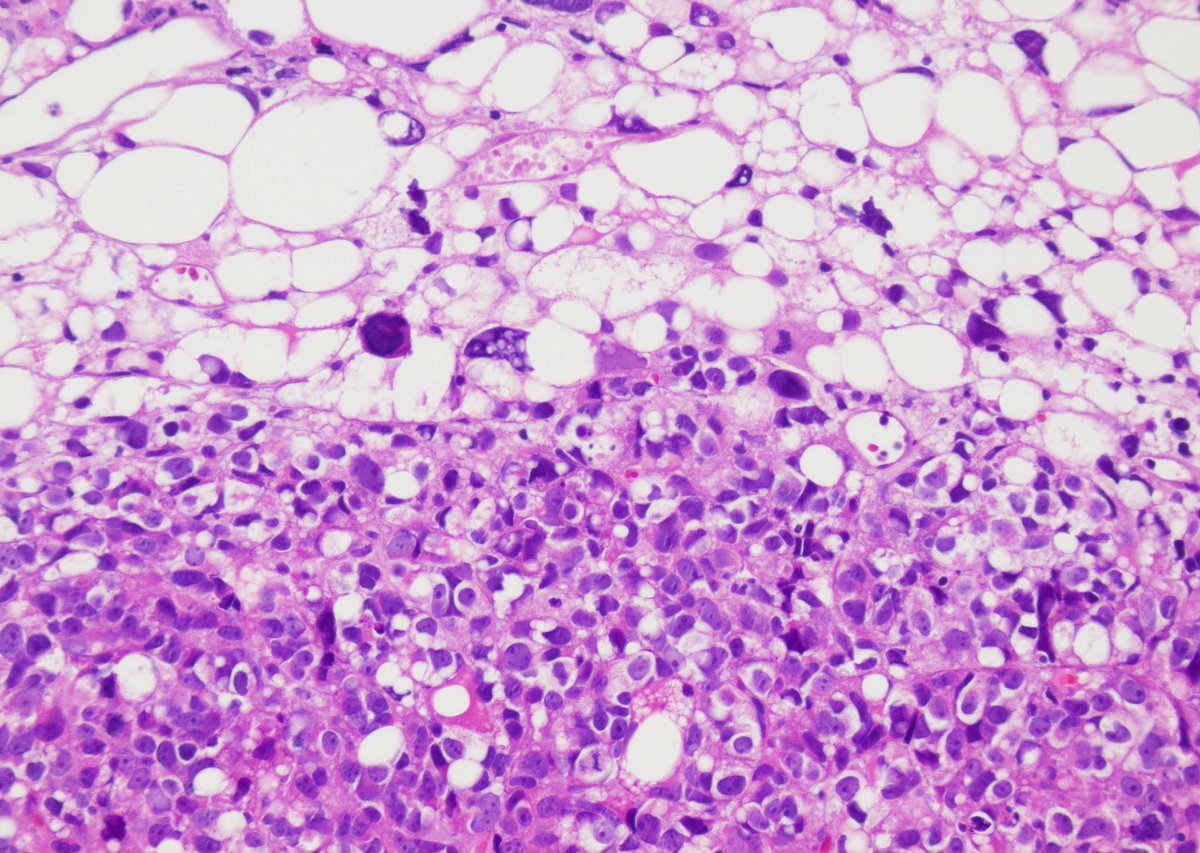

This was a curbside consult from #dermpath. Patient has a history of mastectomy for breast cancer and is now presenting with a chest wall skin nodule. What is your diagnosis? - IHC: p63 @wusm_pathology WashU Medicine Pathology & Immunology Education #breastpath #PathTwitter #PathX